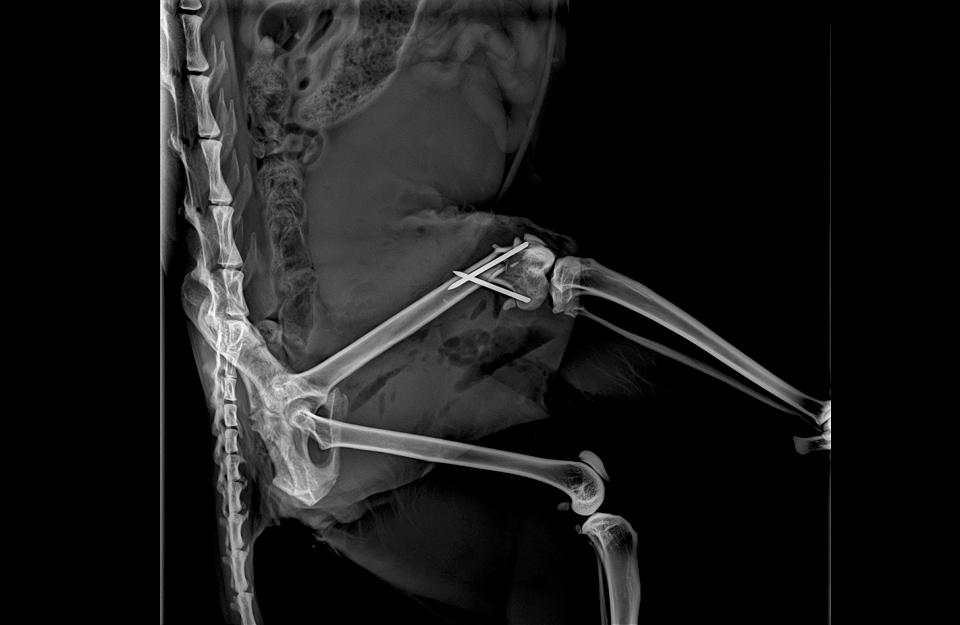

新北市動保處日前深夜接獲民眾通報,瑞芳區逢甲路上有一隻虎斑色小貓,似乎因後肢癱瘓行動不便倒在路邊,救援人員隨即前往將虎斑貓帶回動物醫療中心進行檢傷治療,經醫療中心獸醫師檢查後,發現小貓右後肢近膝蓋處有交錯性骨折,獸醫師群體聯合手術後,目前已恢復健康,並在板橋區家樂福認養會中找到幸福溫暖的家。